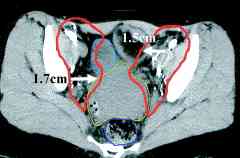

cervix ports, the node positions on CT scans (IJROBP

2002;54:1147) (A) Furthest

distance from lymph node to vessel wall. (B)

Para-aortic lymph node CTV. (C)

Common iliac lymph node CTV. (D)

External iliac CTV, including lateral group. (E) External

iliac CTV, including medial (obturator) group. (F)

Inguinal lymph node CTV. CTV depicted by thick orange line.

Small bowel demarcated by thin magenta, large bowel by thin

blue, rectum by thin dark purple, bladder by thin turquoise, and

uterus by thin yellow-green line. RTOG atlas